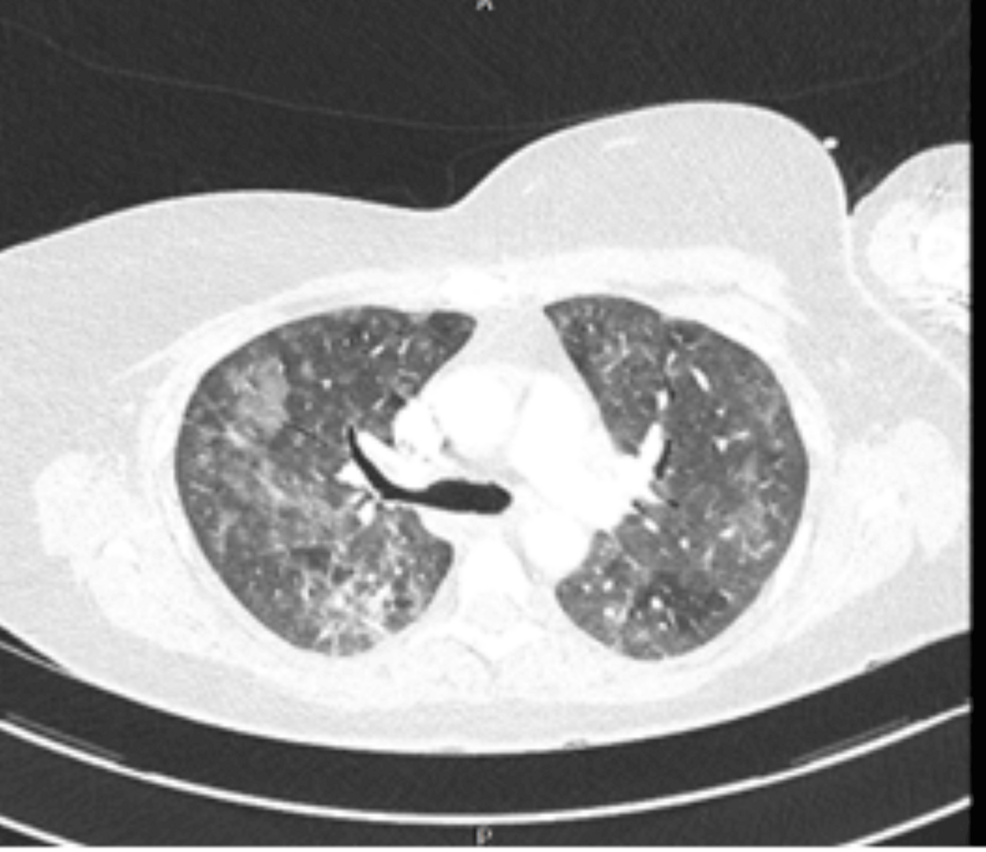

High-resolution Computed Tomography (HRCT): more sensitive for detecting ground-glass opacities and cysts,characteristic of PCP.

Atypical Radiographic Findings: Chest X-rays may show diffuse interstitial infiltrates, but can also be normal or show subtle changes.